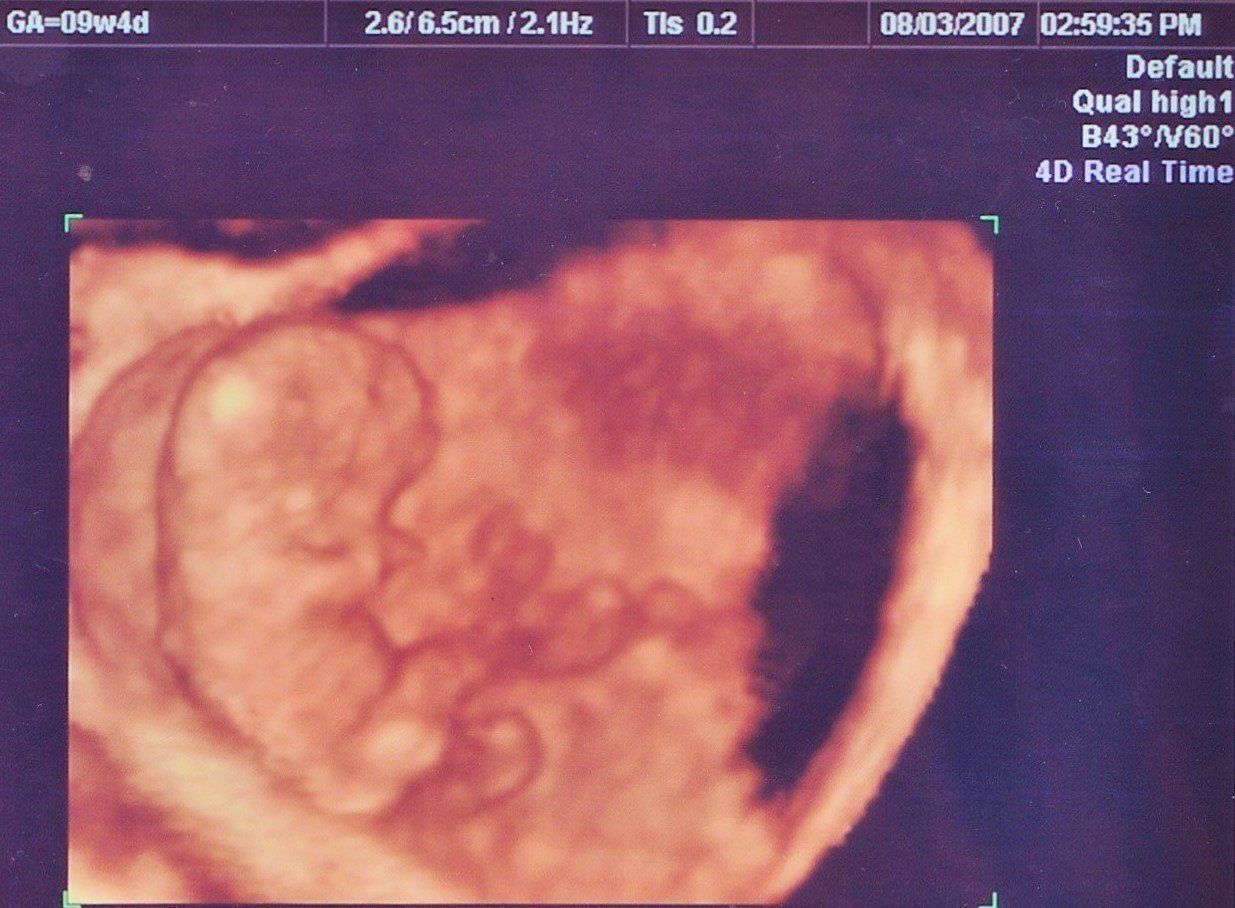

妊娠9週目のエコー写真

4D画像で頭、手、足を見ることができました。枝豆のような頭の形でなんだかかわいい、と早くも親バカ。この時期は、子宮がんや感染症の免疫の有無など、様々な検査を行いました。実母に、私がはしかやおたふく風邪にかかったかなどや、母がどのような妊娠・出産をしたかを教えてもらいました。